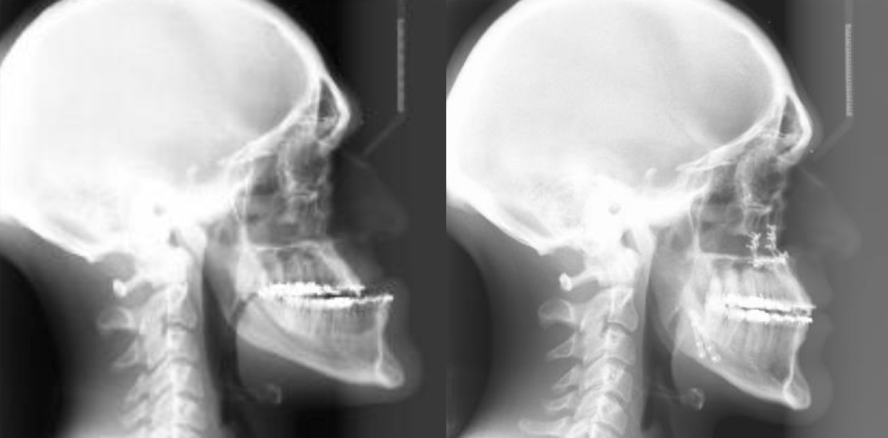

Bei dem vorgestellten Patienten wurde im ersten Schritt im Jahr 2010 der Tumor an der Hirnanhangdrüse über die Nase entfernt. Die klinische Situation bei Erstvorstellung in der Stuttgarter MKG-Spezialsprechstunde (Abb. 1 und Abb. 2). Der Unterkiefer ist zu prominent, der Oberkiefer und das Mittelgesicht liegen zurück. Durch den umgekehrten Überbiss in der Front kann der Patient nicht richtig abbeißen. Das seitliche Röntgenbild bei Erstvorstellung verdeutlicht die skelettale Fehlstellung der Kiefer (Abb. 3).

Im Unterkiefer erfolgte die Schnittführung im Zahnfleisch hinter dem letzten Backenzahn beidseits. Nun wurde der Unterkiefer mit spezieller Technik durchtrennt. Dies erlaubt eine Verschiebung der zahntragenden Basis vom gelenktragenden Knochenabschnitt des Unterkiefers. Bei der Präparation wird der im Unterkieferknochen verlaufende Gefühlsnerv der Unterlippe sorgfältig geschont. Die neue Position wird mit einem zweiten Bissschlüssel, der die endgültige Bisssituation einstellt, zugeordnet und mit Osteosyntheseplatten und -schrauben gesichert. Die Operation ging mit einem stationären Aufenthalt von 5 Tagen einher. Die postoperative Panoramaschichtaufnahme (Abb. 6) zeigt die verlagerten Kiefer und die Stabilisierung mit Titanplatten und -schrauben im Ober- und Unterkiefer. Seitliche Fernröntgenaufnahme zeigt – links vor der Operation – rechts nach der Operation (Abb. 7). Eine deutliche Verlagerung der Kiefer ist zu erkennen. Der Patient kann heute dank der individuellen innovativen Behandlung ein normales Leben führen, die Gesichtsästhetik und Kaufunktion sind vollständig wiederhergestellt. Im Mai des letzten Jahres wurden die Metallplatten in einem ambulanten Eingriff wieder entfernt (Abb. 8 bis Abb. 12).